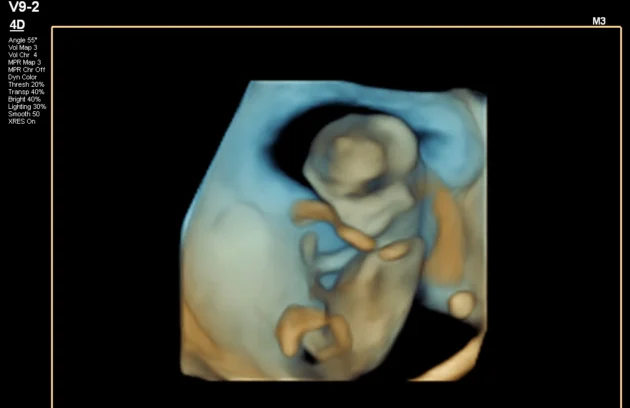

🔹 3D / 4D Ultrasound

3D/4D Ultrasound provides a clear and real-time view of your baby inside the womb. While 3D shows detailed images, 4D allows you to see live movements like smiling or yawning. It enhances bonding between parents and baby while also helping doctors assess physical development. Experience advanced 4D ultrasound in Kathmandu for a memorable and informative pregnancy journey.